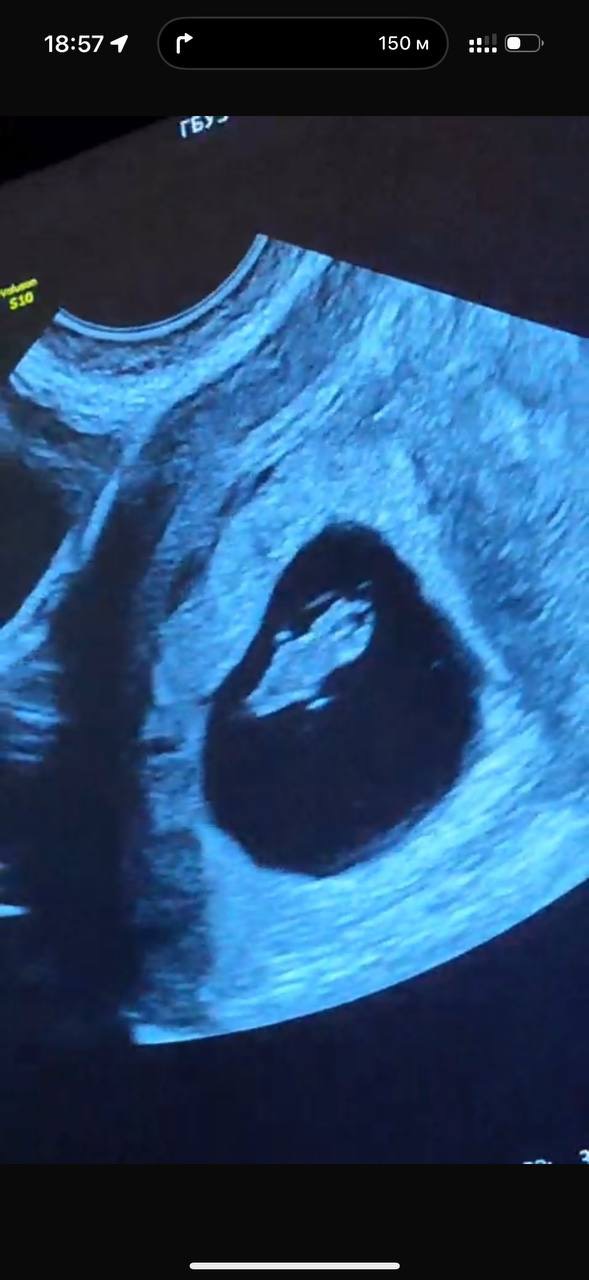

А вот и фото с УЗИ 😍 я даже поверить не могу, что это уже целый организм с бьющимся сердечком, проявляющимися ручками и головой 🥹

Огромное спасибо 😊 когда мне показывали ручки, и показали как бьется сердце , я не верила, что это во мне 🤰🏼 поначалу даже какой-то легкий страх был, но потом муж успокоил сказал «не дури, пойдем поедим нормально»))) а то мы же спортсмены с ним 😃 большое спасибо! Не буду! Даже кондиционеры не включаю лишний раз! И только 23-25 градусов !)